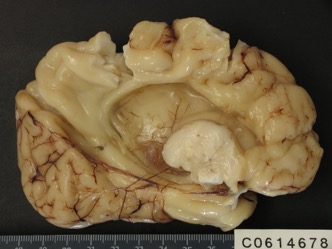

les kystes porencéphaliques et la schizencéphalie

ils résultent de la détersion d’un zone d’infarctus cérébral ; chez le fœtus, les berges de la cavité sont colonisées par la migration des neurones provenant de la zone germinative péri-ventriculaire. ils sont associés à un pronostic péjoratif car :

- il y a perte de substance cérébrale

- il s’est passé un événement grave (infectieux, vasculaire…) qui a pu impacter l’ensemble du cerveau

- il peut exister une pathologie systémique (métabolique…) sous-jacente